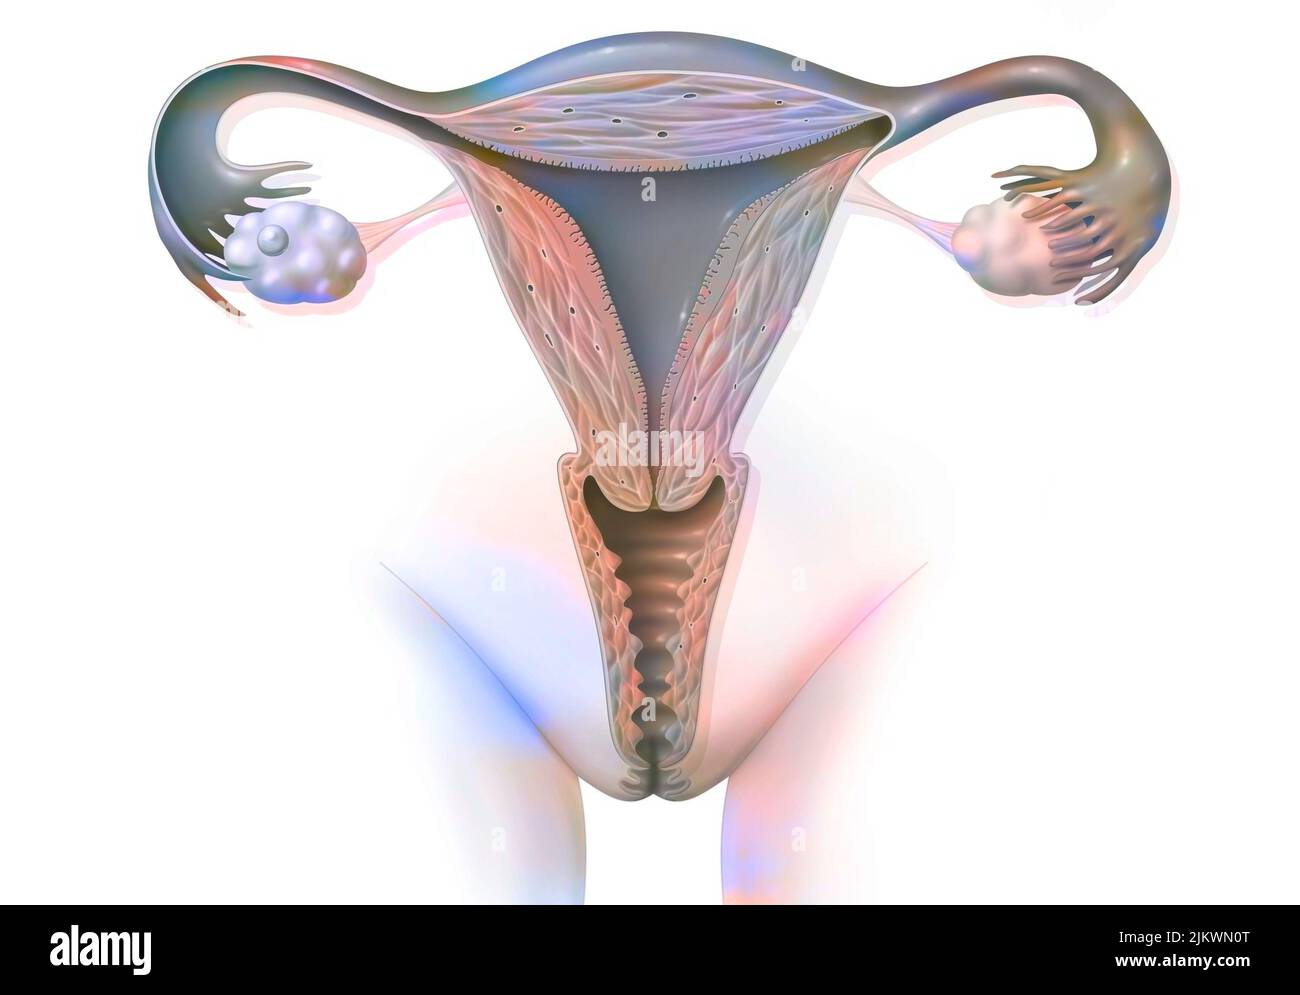

RF2JKWRM1–Vue antérieure des organes génitaux féminins avec vagin, utérus, trompes de Fallope, ovaires.